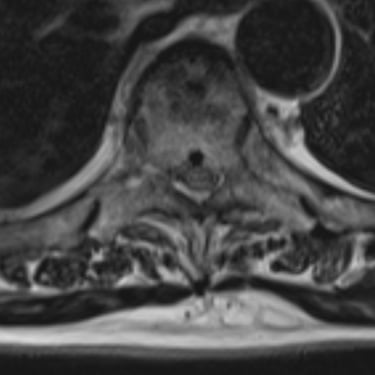

🧠 Listesis L4–L5 con Estenosis Severa: Estabilización con Fijación Transpedicular (FTP) y Fusión Intersomática Transforaminal (TLIF)

La listesis L4–L5 con estenosis severa provoca dolor lumbar e inestabilidad con compresión nerviosa. La fijación transpedicular (FTP) y la fusión intersomática transforaminal (TLIF) permiten descomprimir el canal espinal, estabilizar la columna y mejorar la función de forma segura y progresiva.